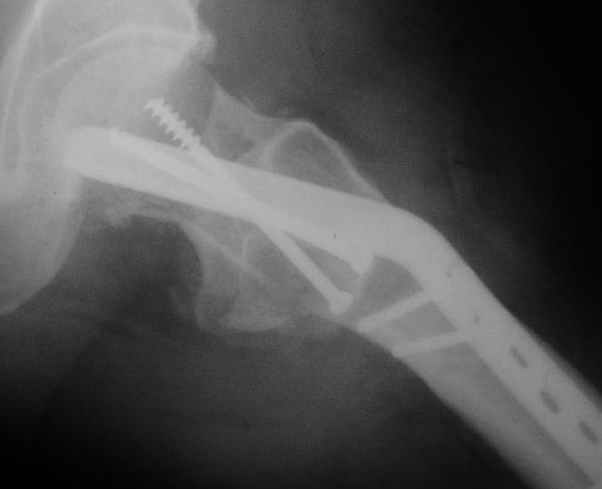

Мужчину 56 лет оперировали у нас в августе 2003 г. - вальгизируюшая остеотомия из-за позднего (через 2 мес. после травмы) поступления с переломом шейки бедра (картинки 1,2). Курильщик, соматической патологии не было. Сейчас поступил с жалобами на проблемы в области тазобедренного сустава, на снимках 3,4 видно вырезывание клинка.Чтоб можно посоветовать в этой ситуации? Заранее спасибо.

A male 56 years old was operated in Aug 2003 - valgus osteotomy performed because of delayed admission with neck fracture (2 months) images 1,2. Smoker, no other major medical problem. Now he re-admitted with the images 3,4.What would you do in the situation?THX in advance.

По-моему, проблема не только в вырезывании клинка, но и в развитии аваскулярного (асептического) некроза головки бедра. Его развитие, кстати, представляется вполне закономерным при предпринятой тактике. Считаю наиболее рациональной тактикой сейчас удаление всех конструкций, реостеотомии (если само не развалится) на прежнем месте и тотальное эндопротезирование с использованием длинной ножки дистальной фиксации с воротником без цемента. Проксимальный фрагмент при этом будет являться аутотрансплантатом, нанизанным на ножку. После операции предписать более щадящий реабилитационный режим (ходьба с костылями месяцев до 4-х).

Сама собой просится идея о тотальном эндопротезировании тазобедренного сустава протезом по типу онкологического (обычный "сажать" уже некуда). Аргументы:

1. Налицо рентгенологическая картина коксартроза. Деформирована головка, суставная щель сужена и т.д.

The osteotomy seems to be showing bony union. (New bone at the medial aspect). There is a big step in the union. The distal fragment is way out laterally.There is overiding of the neck over the head. The screws are out superiorly and the blade also coming out. There is no union of the neck fracture. The head does not seem to be normal- distorted in shape and probably starting of AVN too.

It will be a futile attempt now to get the neck fracture unite. The head has to come out and has to be replaced. Then comes the problem of the malaligned upper shaft. If it has united ( as what I think now) the union has to be undone and fragments aligned before introducing the stem.

The head seems to be lost, the acetabulum has suffered and I would propose a hip replacement, with a long stem, to prevent fracture at the screw holes. With a cables and a cable plate it should be possible to reconstruct the proximal femur.